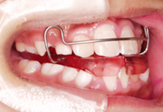

| 治療中 |

| I期治療 |